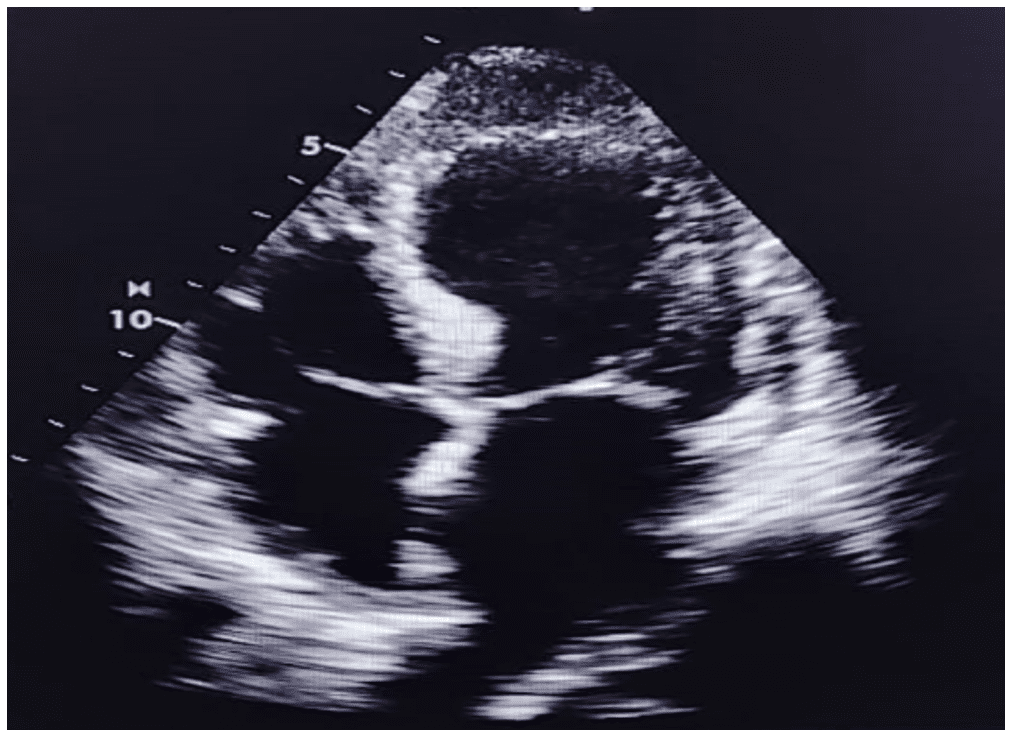

Síndrome de Takotsubo em paciente homem: um relato de caso

A cardiomiopatia por estresse ou Síndrome de Takotsubo (STT) foi descrita há mais de 30 anos e se sustenta até hoje como um importante